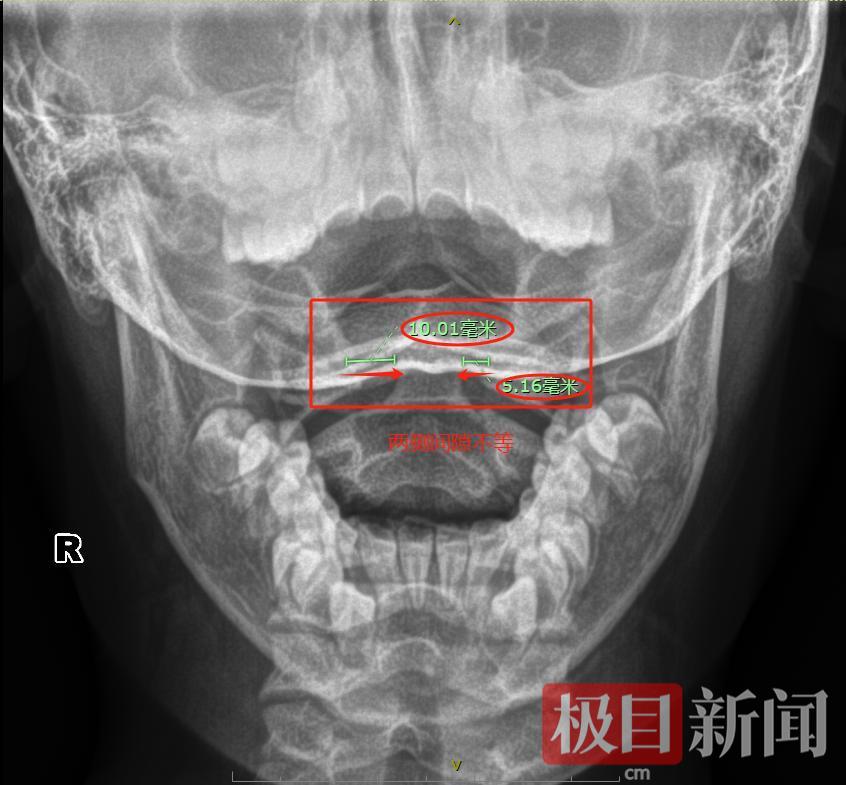

X线显示患儿寰枢关节半脱位

5月27日上午,在体育课上练习广播体操的小沫,做到转头动作时,突然感到颈项部一阵钻心的疼痛,原本灵活的脖子瞬间失去控制,头部不受控制地向右侧歪斜。放学回家后,小沫一直哭着说脖子疼得不敢动,连吃饭拿勺子的动作都做不了。心急如焚的母亲王女士(化姓)当天下午便带着孩子来到武汉市普仁医院小儿骨科就诊。接诊的主治医师汪冰发现,小沫左颈部及胸锁乳突肌按压痛明显,头部向右侧偏斜达30度,颈部屈伸、旋转活动严重受限,连最基本的抬头动作都无法完成。经过X线检查,小沫被确诊为寰枢关节半脱位。

无独有偶,5月29日早晨,7岁的睿睿正在吃早餐,在打了一个喷嚏后,突然捂着脖子哭喊起来,整个人就僵在那里,一动脖子就疼得直掉眼泪,家人立即将他送往医院。汪冰医生检查发现,睿睿虽然生命体征平稳,但颈椎生理曲度存在明显异常,颈部压痛剧烈,屈伸旋转活动受限,孩子疼得连吞咽口水都小心翼翼,生怕牵动颈部。结合影像学检查,睿睿同样被确诊患上了寰枢关节半脱位。医生为其进行了手法整复术,并采取颈托固定治疗。